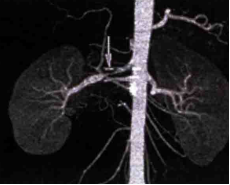

患者于2021年7月29日接受右肾动脉血管扩张成形术。术后逐步停用降压药及补钾药物,短期内在当地医院多次随访血压维持在正常范围。随访情况:术后3个月,血压再次升高,波动于(140~150)/(90~100) mmHg,但多次复查血钾均正常。术后半年门诊复查肾CTA(图3):右肾动脉局部仍存在轻度狭窄,走行较纤细,较术前已明显好转。非卧位2h醛固酮91.32 ng/dl,肾素浓度69.58 ng/L。嘱患者口服钙离子拮抗剂类药物控制血压。术后1年门诊复查肾CTA(图4):右肾动脉狭窄程度大致同前,未进一步加重。血压维持在(120~130)/(90~100) mmHg,多次复查血钾及肾功能均正常。

图4. 术后一年复查肾CTA